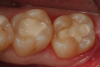

Fig 13. After controlling any bleeding from the exposure site with sodium hypochlorite on a cotton pellet,  a bioactive cavity liner (TheraCalTM LC, Bisco Dental Products) was then placed over the exposure site and light cured.  Next, a bioactive “dentin replacement” material (TheraBase, Bisco Dental Products) was used to base both cavity preparations to a more ideal depth just apical to the dentinoenamel junction.

Figure 13